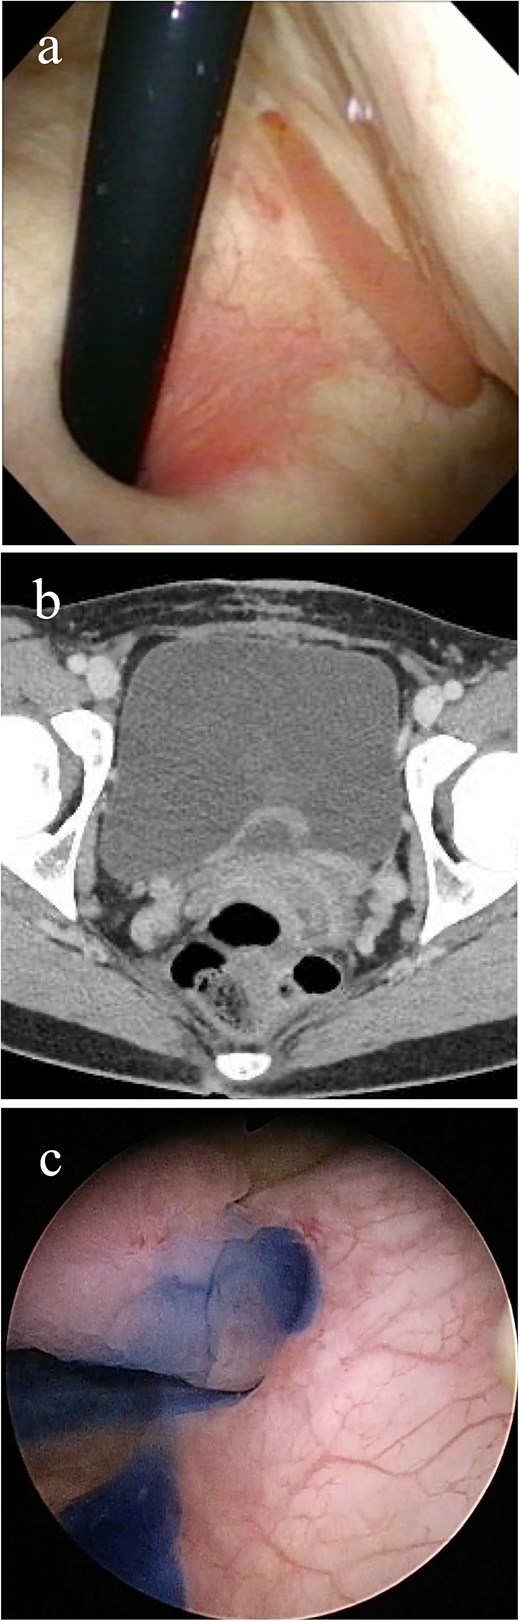

Imaging study findings. (a) Cystoscopy finding. Cystoscopy revealed that a tumor protruded from the left ureteral orifice into the bladder lumen, showing serpentine locomotion with respiratory movements. (b) Contrast enhanced computed tomography finding. Soft tissue shadow was detected around the left ureteral orifice, revealing a long thin tumor. (c) Indigo carmine was excreted through the left orifice that is occupied by the tumor.

The patient underwent detailed endoscopy in the operating room (Video 1). The indigo carmine test revealed patency in the ureteral orifice occupied by the tumor (Fig. 1c). A ureteroscope was inserted along the tumor into the left ureter. The lower ureter was occupied nearly completely by the tumor, but the ureteroscope could pass through the small gap between the tumor and the ureteral wall. As the scope reached the mid-ureter, the root of the tumor eventually became thinner, and a single narrow base of the tumor was identified. FEP was diagnosed based on the characteristic surface findings and root shape of the tumor. Because this polyp could be safely removed ureteroscopically, ureteroscopic resection was performed using a Holmium: YAG Laser (0.3 J, 10 Hz). Electrocautery was applied to the base of the polyp, and the coagulation area was kept as small as possible. Finally, the polyp was resected and extracted entirely from the ureter and into the bladder lumen using forceps. A double-J stent was inserted, and the ureteroscopic procedure was completed. The stent was removed a month after the surgery. Her gross hematuria stopped, and she reported no complications. Histopathological examination revealed a 9.5 cm tumor and a polyp with edematous stroma, which was confirmed to be ureteral FEP (Fig. 2a and b).